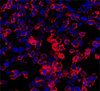

Methodologically, the study used sophisticated cell differentiation and isolation techniques. Stem cell cultivation conditions capable of activating the necessary signals towards the differentiation of acinar pancreatic cells have been optimised. Through viral vectors that express transcription factors that are key for pancreatic development, the process of obtaining a sufficient amount of these cells has been amplified and, ultimately, a painstaking genetic selection and cell lineage purification has been assured for the study. Through the integration of these approaches, the isolation of highly efficient cells with acinar phenotype- functionally similar to acinar pancreatic cells- has been obtained. The importance of this study lies in its distinction from previous studies carried out using primary cultures: the cells generated do not display a ductal intermediary phenotype. This fact has made it so that a new model has been established, in vitro using non-tumour cells, for the acinar differentiation study, a deregulated process in many diseases of the exocrine pancreas.

The fact that cells with an immature phenotype have been generated gains relevance since it was demonstrated that immature acinar cells are more susceptible to oncogenic transformation than mature cells and therefore will serve as a base for understanding the nature of tumour precursors.